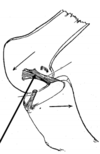

Describe the knee joint capsule

The capsule is attached around the articular margins of the knee joint encircling the tibiofemoral articulations and incorporates the patellofemoral joint.

The joint capsule is reinforced around all sides of the joint by muscles and/or the tendinous insertions of the muscles.

Describe the anterior support of muscles

The quadricepts muscle terminates in the quadricepts tone that lines the top of the patella ending in the patellar tendon with retinacular fibres running along side it (anteriolateral aspects)